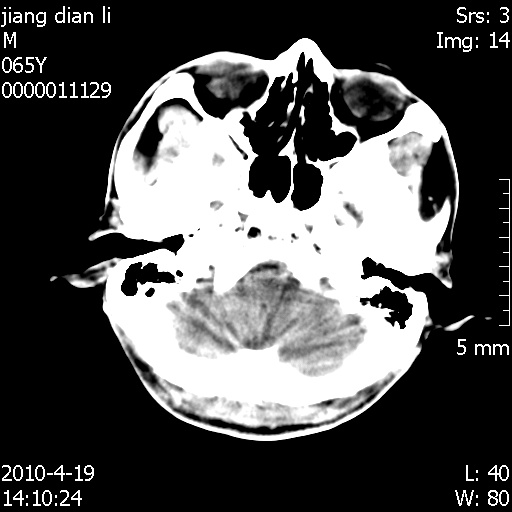

老年男性,突发左下肢无力1天,其余有价值的检查都没有。平扫ct值大约60hu,增强后ct值没什么改变,请大家讨论一下这个病例是什么?说明诊断理由。

左小脑、右大脑顶叶多发圆形高密度病灶,其周环状低密度影。考虑多发脑出血。隔期观察。

幕下的是血,幕上这个学习中

今天遇到临床医生,询问病人情况,病人已经死亡。

最后看到的病人右侧瞳孔呈针尖大小,估计是继发脑干梗死,而非脑疝死亡。

其他检查也没有来得及做。

遗憾! 复习了复查片:发现顶叶出血灶破入侧脑室,侧脑室体部见少许高密度。